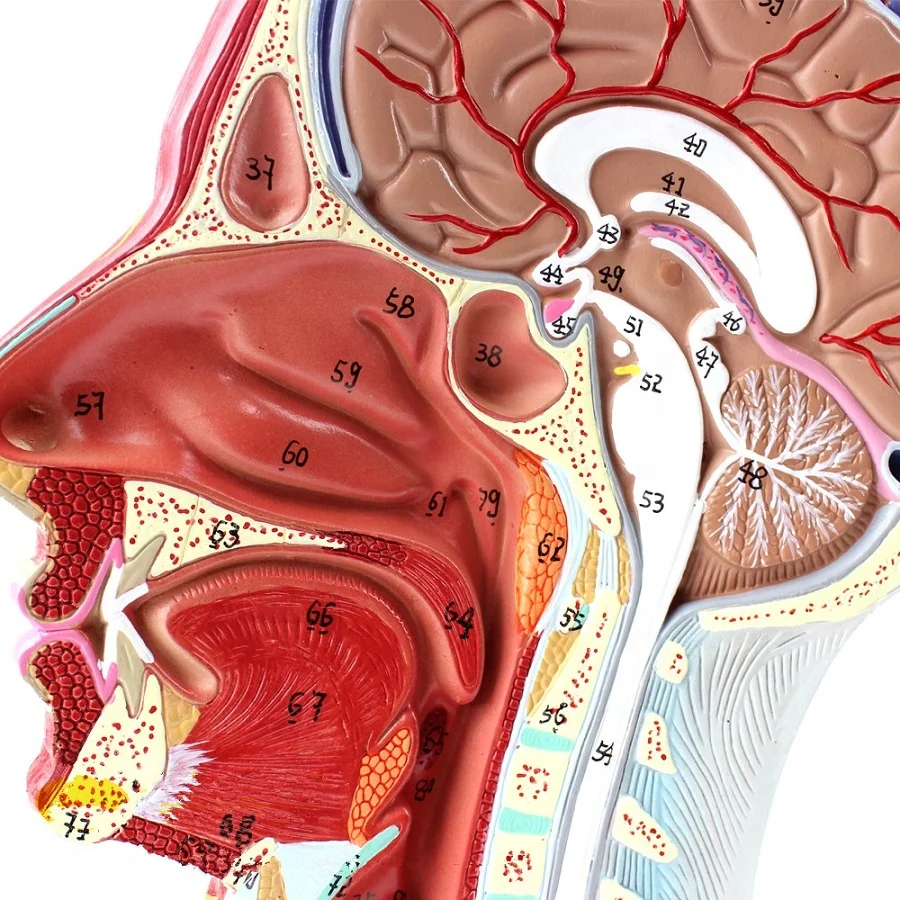

1. The double sided model shows median sagittal sectioned head anatomy, displaying brain, nasal cavity, oral ccvity and pharynx cavity.

2. Anatomically mimic muscular system with the main superficial arteries, veins and nerves and the area of the neck are demonstrated.

3. 100 positions are displayed.

Size:life size 27*10*20cm